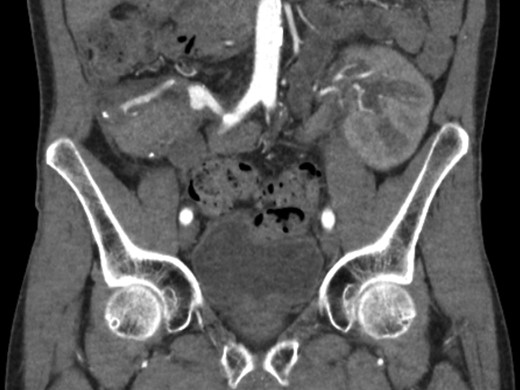

Because of the patient’s stability and desire to keep his well-functioning pancreatic graft, a close-monitoring policy was followed and the graft was left in place. Several follow-up CT angiographies showed no sign of endoleak or recurrent aneurysm (Fig. 4). Vitamin K antagonists were stopped and replaced with acetyl salicylic acid prophylaxis. After 12 months of follow-up, the patient is still well with excellent kidney and pancreas graft function.

Follow-up CT scan showing a patent SMA tract with stent in position and no signs of endoleak.